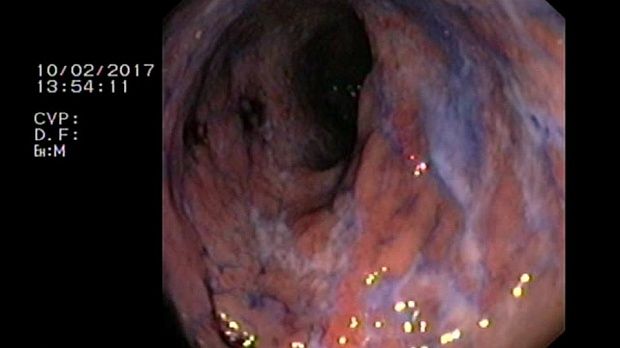

2 мл ( это мин сум, а мы делаем до 10 мл 3% перекись+200 мл физ раствора